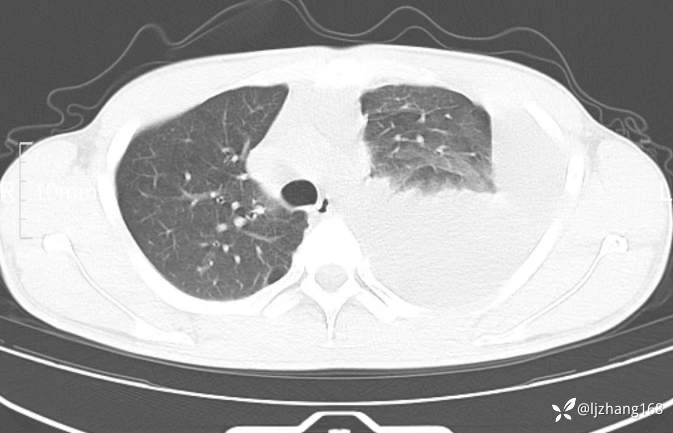

辅助检查:胸部CT:左侧大量胸腔积液。胸水常规:嗜酸性粒细胞 74 %、总细胞数 29600×10^6/L、白细胞数 1600 ×10^6/L、淋巴细胞 20 %。2023-12-17 胸水生化:腺苷脱氨酶 58.6 U/L、总蛋白 59.7 g/L。抗结核抗体(痰液)、(痰液)抗酸染色、尿常规、大便常规、未见明显异常。